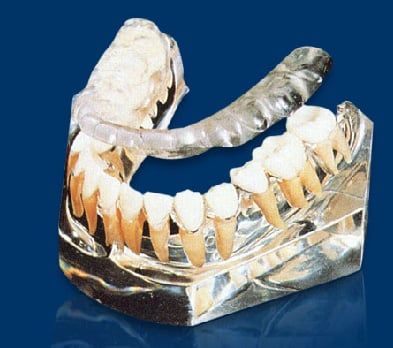

They are the two joints which connect the lower jaw to the temporal bone at the side of the head. If you place your fingers just in front of your ears and open your mouth, you can feel the joint on each side of the head. Because these joints are flexible, the jaw can move smoothly up and down and side to side, enabling us to talk, chew and yawn. When the TMJ is not functioning normally and it is not within its physiological limits, it creates a condition called TMD, or Temporomandibular Dysfunction.

TMD is a group of conditions resulting from not having a normal function or "comfortable" positioning of the TMJ, and will present as a cycle of pain, muscle spasms and jaw problems. When teeth are missing, out of alignment, crowded or misshaped, chewing and biting cannot be achieved in a balanced way, so the TMJ and the muscles of chewing try to compensate for this unbalanced movement which results in symptoms that will confirm the presence of TMD.

TMD is a group of conditions resulting from not having a normal function or "comfortable" positioning of the TMJ, and will present as a cycle of pain, muscle spasms and jaw problems. When teeth are missing, out of alignment, crowded or misshaped, chewing and biting cannot be achieved in a balanced way, so the TMJ and the muscles of chewing try to compensate for this unbalanced movement which results in symptoms that will confirm the presence of TMD.

When teeth are missing, or out of alignment, it causes the jaw to shift positions and the muscles to work harder to chew, swallow, bite...etc and eventually will cause: muscle spasms, tension and pain.

Muscle tension and misplaced TMJ could cause the TMJ disc to be pulled out of place which will result in pain, clicking and popping in the TMJ.